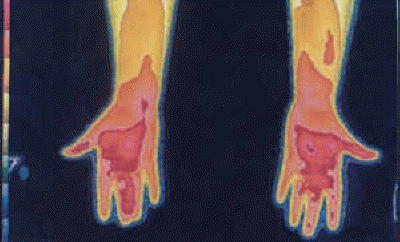

Thermography of the Right Hand (a.k.a.) "Boxers Hand Deformity." CRPS of seven years duration due to right hand injury. Two years of unsuccessful operations at right carpal tunnel, and five years of immobilization of hand have resulted in "Boxers Hand Deformity" and ultimate amputation.